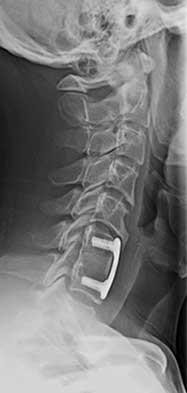

The process at C5-6 shown in Figures 36a and 36b is from radiographs taken in 2006 and 2009, and can occur over time following an anterior cervical discectomy and fusion. At what rate per year is this thought to occur?

A B

The process shown in the figures is that of degenerative change adjacent to an anterior cervical discectomy and fusion. The observed rate of degenerative adjacent changes is estimated at 2% to 3% per year following a single-level fusion. These changes are partly related to the natural aging process or degenerative process and can occur regardless of an adjacent fusion, but the influence of a solid adjacent fusion with the increased stress at the next level is thought to be a contributor.